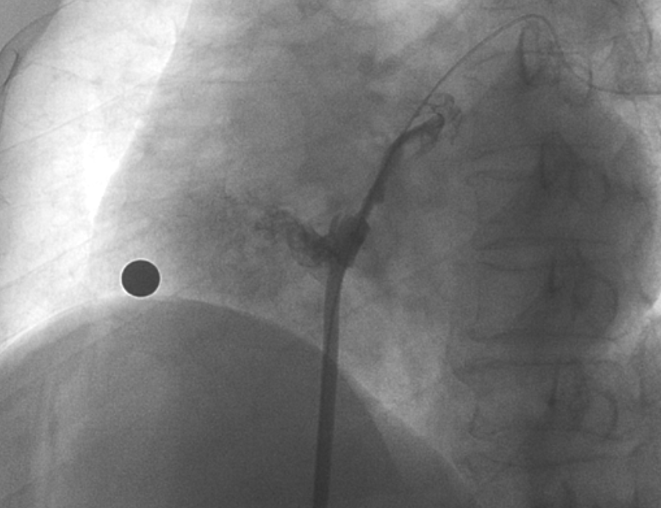

造影顯示長隧道型PFO

在本次植入手術(shù)中,接受介入封堵術(shù)的是一名卵圓孔未閉(長隧道型)的患者。患者60歲,男性,7年前曾診斷腦梗死,此次因新發(fā)腦梗死入院,無房顫及頸動脈狹窄;經(jīng)胸心臟超聲和心臟聲學(xué)造影檢查提示卵圓孔未閉,Valsalva動作后心房水平大量右向左分流。經(jīng)儲慧民教授團(tuán)隊(duì)評估,結(jié)合相關(guān)病史并考慮PFO及不明原因卒中,遂決定對患者開展經(jīng)皮PFO封堵術(shù)。

術(shù)中造影顯示患者為PFO且長隧道型,目前市場上已商業(yè)化的PFO封堵器難以滿足該患者解剖結(jié)構(gòu)封堵需求。迪創(chuàng)醫(yī)療自主研發(fā)的OmniSeal PFO封堵器自適應(yīng)性雙盤貼合設(shè)計(jì)能廣泛適應(yīng)不同PFO隧道長度的解剖結(jié)構(gòu)和形態(tài),其雙盤外包覆式阻流和隧道內(nèi)填充阻流相結(jié)合的雙重阻流設(shè)計(jì),可為此患者實(shí)現(xiàn)有效封堵。與此同時,OmniSeal首創(chuàng)的完全可穿刺式設(shè)計(jì),也為此患者最大程度地保留了房間隔區(qū)域穿刺通道,以實(shí)現(xiàn)全兼容未來可能的左心系統(tǒng)二次介入術(shù)。術(shù)終造影和心臟超聲顯示封堵完全、效果良好。作為OmniSeal的首例臨床應(yīng)用,本次手術(shù)的順利完成和優(yōu)異效果充分體現(xiàn)了產(chǎn)品的設(shè)計(jì)創(chuàng)新優(yōu)勢。